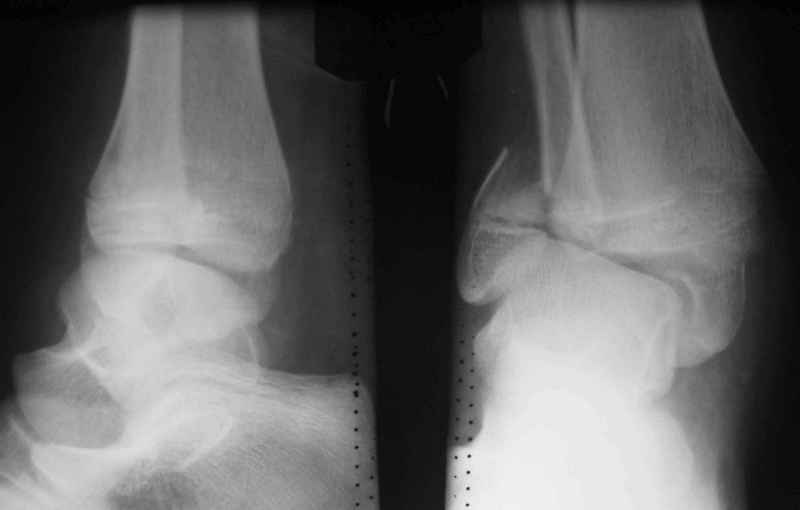

Здравствуйте, коллеги.Обратились родители мальчика 15 лет. Сами врачи.В июле 2009 года - перелом лодыжек.

Лечили спорно, на мой взгляд. В результате - - сращение наружной лодыжки с укорочением, подвывих голеностопа кнаружи (вальгус) в итоге компенсаторно передний отдел стопы ставит на варус. Нагрузку ограничивает.

Снимки в приложении.

Следуя принципам восстановительной хирургии, необходимо дозированное повреждение опорного аппарата- возвращение в преморбидное состояние с последующим восстановлением структуры(Илизаров как метод выбора).

С этой целью предлагаем восстановить анатомию м/берцовой кости, следствием чего будет возможность выставить центр тарана по оси голени, устранить эквинус и суппинацию переднего отдела стопы.